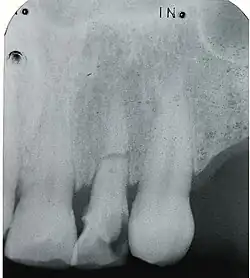

Frontzahntrauma an drei oberen Inzisiven (11,21 und 22)

Als Frontzahntrauma oder Frontzahnverletzung wird die Verletzung der Frontzähne und der benachbarten Strukturen durch Gewalteinwirkung bezeichnet. Frontzähne sind Schneidezähne und Eckzähne. Beim Frontzahntrauma sind fast ausschließlich die oberen Schneidezähne betroffen und nur sehr selten die Eckzähne oder die unteren Schneidezähne. Ursächlich für ein solches mechanisches Trauma sind meist Schlag, Stoß oder Fall.

Die Frontzahntraumen werden in Zahnstauchungen, Zahnluxationen und Zahnfrakturen unterteilt, letztere nochmals in Kronenfrakturen und Wurzelfrakturen.